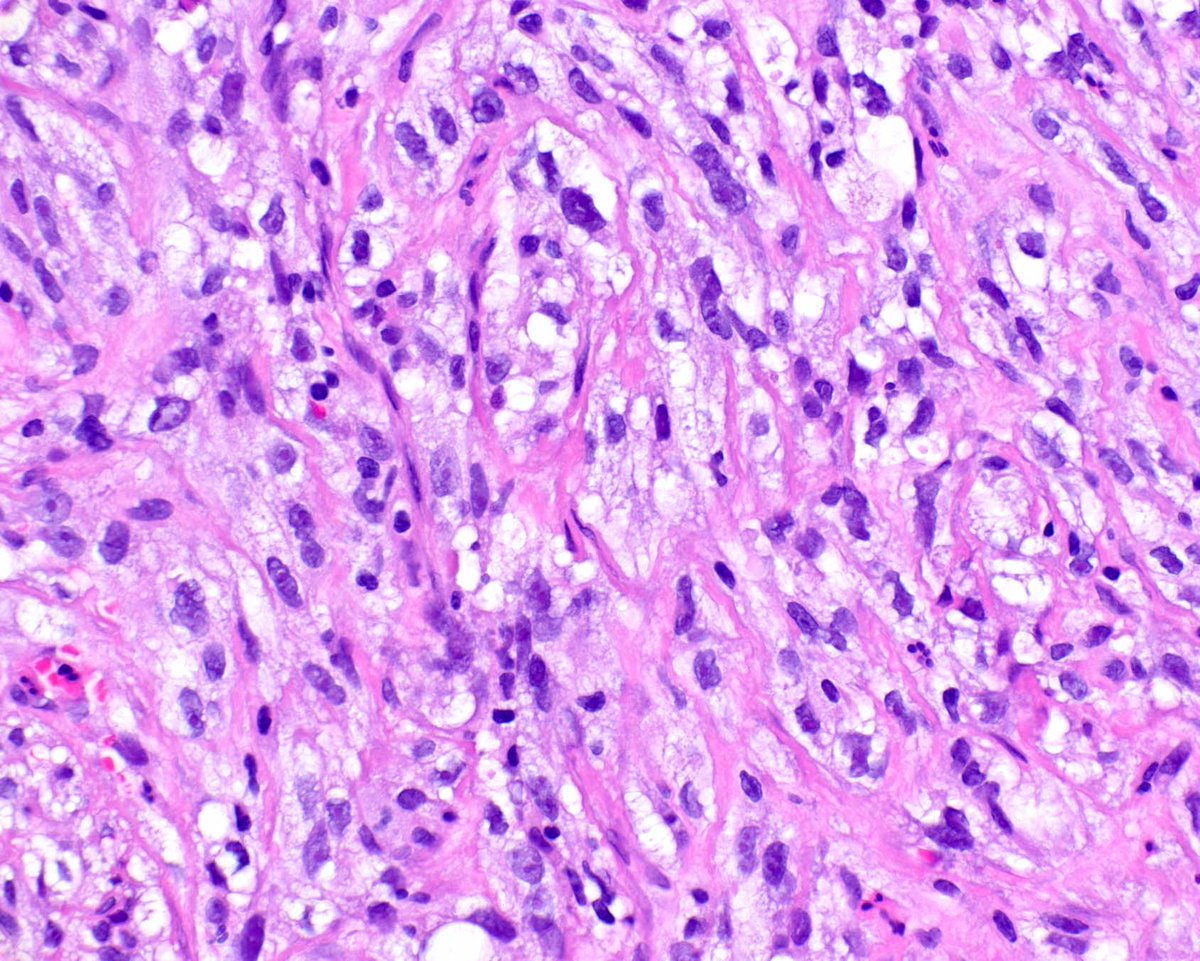

This sarcomatoid renal cell carcinoma was difficult for me. I initially thought it was a PEComa and added pertinent immunohistochemistry - all negative (HMB45, smooth muscle actin, cathepsin K). Then I woke up and added a keratin!

2

40

149